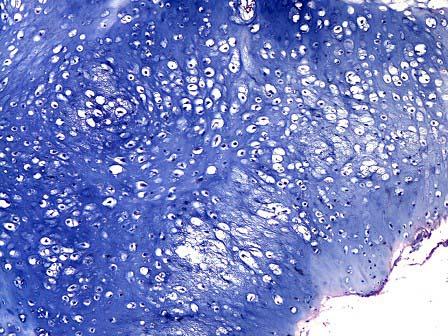

问题 患者,男,21岁,右手示指指骨无痛性肿胀,X线示右手示指指骨骨髓腔内有椭圆的透亮点,呈溶骨破坏。活检见瘤细胞由成熟的透明软骨组成,呈不规则分叶状,由疏松的纤维血管间质包绕,如图1、2所示,该病变的最佳诊断是 ( )

选项 A.骨瘤 B.软骨瘤 C.骨软骨瘤 D.骨囊肿 E.骨样骨瘤

答案 B